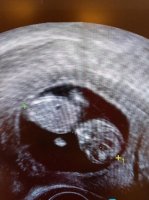

Her er nurket som jeg fikk kikket litt på i går! ❤ regnet ut til å være 9+2 i går! :) en dag fra eller til spiller ingen rolle ❤